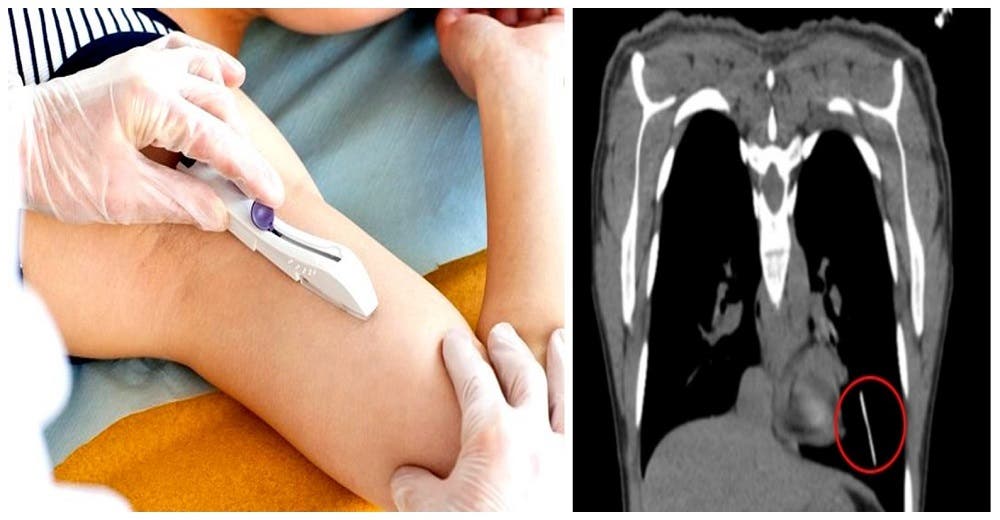

Le colocan un implante anticonceptivo en el brazo y la operan de urgencia – No lo encontraban